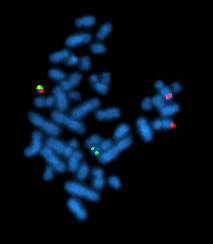

- تشخيص المرض عن طريق التهجين الموضعي المتألق (Flourscent in situ hybridization) لرؤية الإنتقال المكاني بين الكروموسومين.